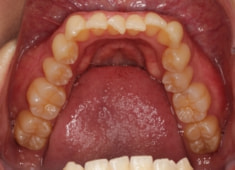

治療後(2年後)

治療開始から24ヶ月後